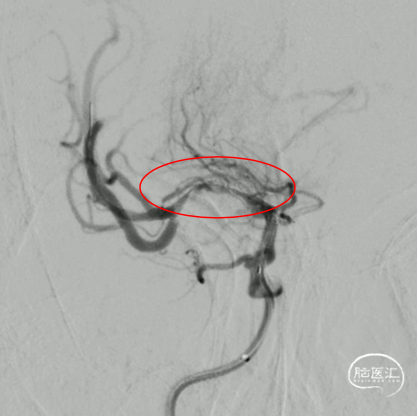

右侧大脑中动脉起始部闭塞,左侧前交通开放,左侧大脑前动脉通过软膜支代偿,大脑后动脉通过软膜支代偿,侧支代偿可,考虑粥样硬化合并急性闭塞的可能。

取栓后造影,M1再通,局部狭窄可能,前向血流延迟。

M1局部狭窄,合并小血栓可能。

M1局部重度狭窄。